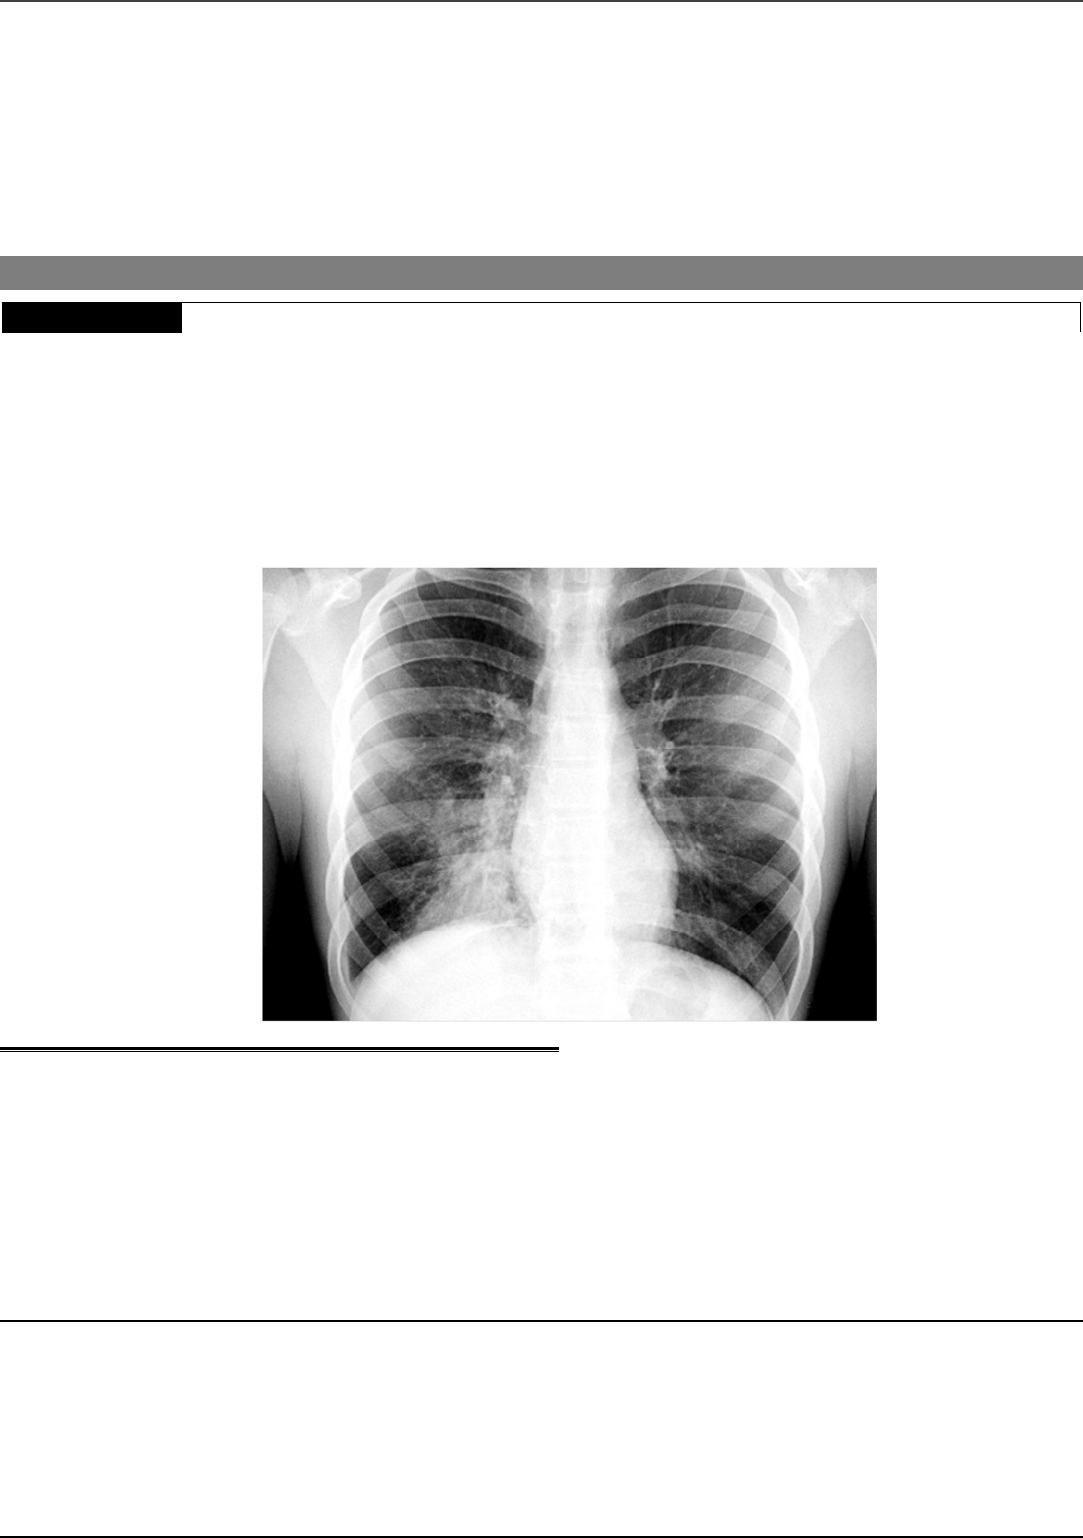

<p>CEBRASPE – CAGEPA – Edital: 2024</p><p>• Nesta prova, faça o que se pede, usando, caso deseje, os espaços para rascunho indicados no presente caderno. Em seguida,</p><p>transcreva os textos para a FOLHA DE TEXTOS DEFINITIVOS DA PROVA DISCURSIVA, nos locais apropriados, pois</p><p>não será avaliado fragmento de texto escrito em local indevido.</p><p>• Qualquer fragmento de texto além da extensão máxima de linhas disponibilizadas será desconsiderado. Também será</p><p>desconsiderado o texto que não estiver escrito no respectivo espaço destinado na Folha de Textos Definitivos.</p><p>• Na Folha de Textos Definitivos, a presença de qualquer marca identificadora nos espaços destinados à transcrição dos textos</p><p>definitivos acarretará a anulação da sua prova discursiva.</p><p>• Em cada questão discursiva, ao domínio do conteúdo serão atribuídos até 10,00 pontos, dos quais até 0,50 ponto será atribuído ao</p><p>quesito apresentação (legibilidade, respeito às margens e indicação de parágrafos) e estrutura textual (organização das ideias em</p><p>texto estruturado).</p><p>-- PROVA DISCURSIVA --</p><p>QUESTÃO 1</p><p>Um paciente de 43 anos de idade, sem comorbidades, alergias ou tratamentos no último ano,</p><p>apresenta quadro de adinamia, anorexia, picos febris (até 38,5 °C), tosse produtiva com escarro</p><p>purulento e cansaço aos esforços há dois dias. No exame físico, encontrava-se febril, acianótico, com</p><p>frequência cardíaca de 108 bpm, frequência respiratória de 21 irpm, saturação de oxigênio em ar</p><p>ambiente de 95% e pressão arterial de 126 mmHg × 78 mmHg. A ausculta pulmonar revelou estertores</p><p>crepitantes em terço inferior do pulmão direito. O restante do exame físico não revelou alterações</p><p>significativas. Os resultados de hemograma realizado indicaram 13.000 leucócitos, sem desvio à</p><p>esquerda, ureia de 36 mg/dL e creatinina de 0,9 mg/dL. O paciente foi submetido a radiografia de tórax,</p><p>cujo resultado está apresentado a seguir.</p><p>Considerando o caso clínico hipotético apresentado, responda, justificadamente, de acordo com as recomendações da sociedade</p><p>brasileira que trata da patologia em questão, às seguintes perguntas.</p><p>1 Qual é o diagnóstico? [valor: 2,00 pontos]</p><p>2 Quais dados do quadro clínico do paciente justificam esse diagnóstico? [valor: 2,00 pontos]</p><p>3 É(São) necessário(s) outro(s) exame(s) complementar(es) para que o paciente inicie o tratamento? [valor: 1,80 ponto]</p><p>4 Qual é a terapia medicamentosa recomendada? [valor: 1,90 ponto]</p><p>5 Em qual regime essa terapia deve ser administrada: via ambulatorial, emergência ou internação hospitalar?</p><p>[valor: 1,80 ponto]</p><p>CEBRASPE – CAGEPA – Edital: 2024</p><p>QUESTÃO 1 – RASCUNHO</p><p>1</p><p>2</p><p>3</p><p>4</p><p>5</p><p>6</p><p>7</p><p>8</p><p>9</p><p>10</p><p>11</p><p>12</p><p>13</p><p>14</p><p>15</p><p>CEBRASPE – CAGEPA – Edital: 2024</p><p>QUESTÃO 2</p><p>Exposição curta também prejudica</p><p>Estudo mostra que respirar partículas tóxicas por dias ou mesmo horas também impacta</p><p>negativamente a saúde, registrando-se mais de 1 milhão de mortes precoces atribuídas à poluição aguda</p><p>do ar.</p><p>Correio Braziliense, 6/3/2024 (com adaptações).</p><p>Considerando que o fragmento de texto precedente tem caráter unicamente motivador, redija um texto dissertativo a respeito das</p><p>pneumoconioses relacionadas ao trabalho. Ao elaborar seu texto, atenda ao que se pede a seguir.</p><p>1 Defina pneumoconioses. [valor: 2,00 pontos]</p><p>2 Apresente dois exemplos dessas patologias e seus respectivos agentes causadores relacionados ao</p><p>trabalho. [valor: 2,50 pontos]</p><p>3 Aponte as duas principais complicações oncogênicas das pneumoconioses decorrentes da exposição à poeira de</p><p>sílica. [valor: 2,00 pontos]</p><p>4 Indique o principal exame complementar para avaliação da função pulmonar em pacientes com pneumoconioses e os</p><p>parâmetros básicos para classificação dos tipos de doenças. [valor: 3,00 pontos]</p><p>QUESTÃO 2 – RASCUNHO</p><p>1</p><p>2</p><p>3</p><p>4</p><p>5</p><p>6</p><p>7</p><p>8</p><p>9</p><p>10</p><p>11</p><p>12</p><p>13</p><p>14</p><p>15</p>